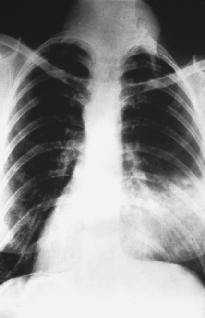

- Penyakit paru- paru yang diakibatkan serangan bakteri Mycobacterium tuberculosis.

- Difusi oksigen akan terganggu karena adanya bintil- bintil atau peradangan pada dinding alveolus.

- Jika bagian paru- paru yang diserang meluas, sel- selnya mati dan paru- paru mengecil.

- Akibatnya napas penderita terengah- engah.

b. Tuberkolosis / TBC, merupakan penyakit yang disebabkan oleh baksil yangmengakibatkan bintil-bintil pada dinding alveolus.